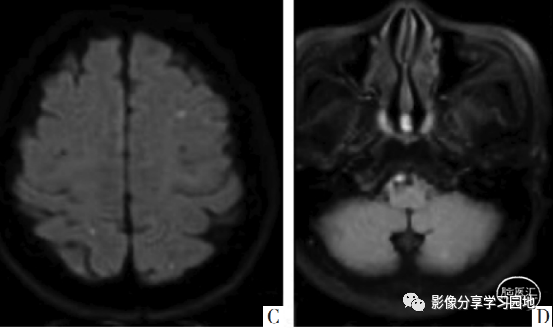

▶ 病例 下图 女,58岁、头晕入院 MRI DWI显示双侧小脑半球多发点状及斑片状高信号,提示急性脑梗死的表现。生化检查显示D-二聚体升高,C反应蛋白增高,后检查发现有子宫内膜癌。